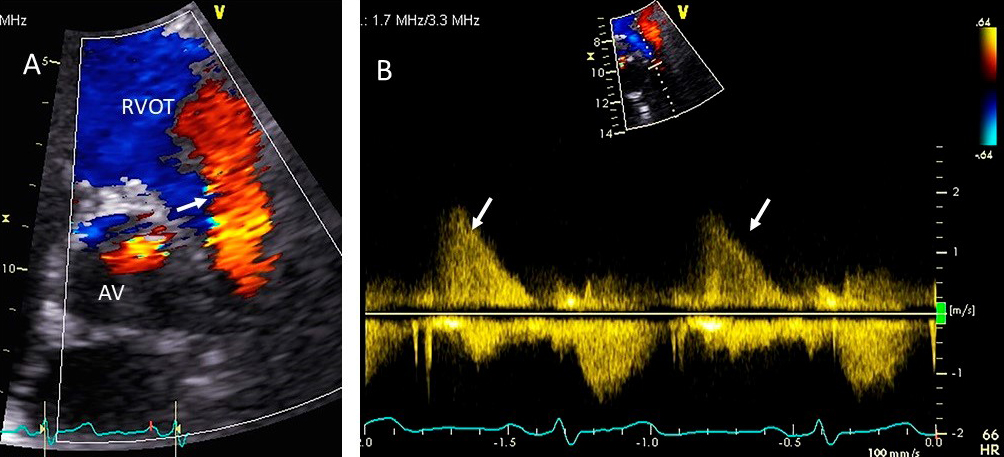

PR is diagnosed with color Doppler revealing diastolic flow in the RV outflow

tract (Fig. 11). In severe PR with normal PA pressures (e.g., primary PR), the

color jet has low velocity with laminar flow and the duration of the flow can be

misleading, as severe PR may lead to rapid equalization of the RV pressure with

diastolic pulmonary artery pressure, and thereby lead to a very short duration of

flow [67]. In secondary PR from pulmonary hypertension, the jet is aliased and

usually holodiastolic [68]. Severe PR from primary or secondary causes has an

intense spectral Doppler signal. Other parameters to assess PR severity include

PR jet width: if it occupies

Fig. 11.Pulmonic valve regurgitation. (A) TTE basal short axis view

showing color Doppler of pulmonic valve (in the long axis view) and aortic valve

in the short axis view. There is severe pulmonic regurgitation as shown by a wide

diastolic jet in the RVOT occupying